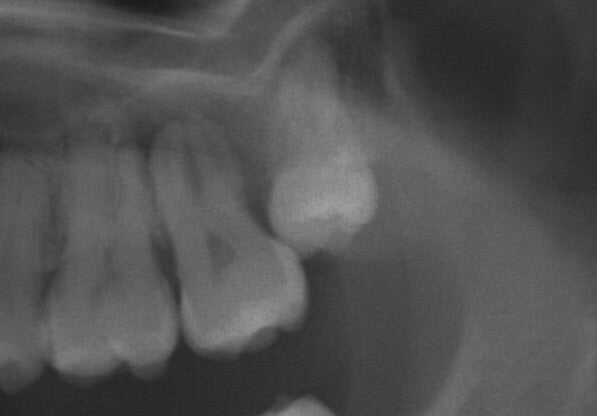

<上顎のケース・抜歯前>

この症例も歯が潜っているため他院で麻酔が効かなく痛かった事に加えて、抜歯が困難で施術を中断されたケースです。

その経験から抜歯がトラウマになり、当院へ相談しにいらっしゃいました。